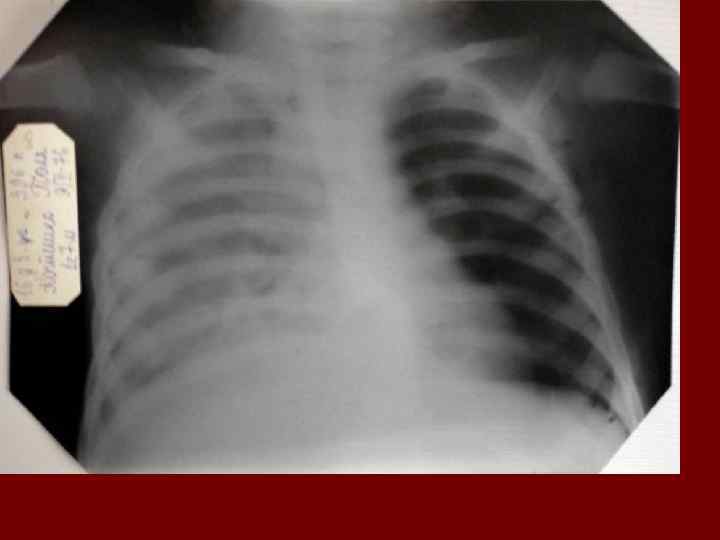

Долевая пневмония характеризуется лобарным пневмоническим инфильтратом. Крупозная ( пневмококковая) пневмония диагностируется прежде всего по клиническим данным. Крупозная пневмония сохраняет свою типичную картину пневмококковой пневмонии: острое начало с характерными клиническими данными, циклическое течение, несклонность к деструкции, гомогенной и лобарной инфильтративной тенью при рентгенологическом исследовании. Вместе с тем, широкое использование антибиотиков способствовало значительному снижению числа крупозных пневмоний у детей. Интерстициальная – редкая форма пневмоний, при которой оказывается поражен прежде всего интерстиций. Как правило, интерстициальная пневмония обусловлена вирусами, пневмоцистами, внутриклеточными микроорганизмами и грибами.

Морфологическую форму пневмонии определяют по клинико – рентгенологическим данным: выделяют очаговую, очагово – сливную, долевую ( крупозную), сегментарную и интерстициальную пневмонии. Очаговая – наиболее распространенная форма. Пневмонические очаги чаще бывают размером 1 см и более. Очагово – сливная – инфильтративные изменения в нескольких сегментах или во всей доле легкого, на фоне которых могут быть видны более плотные участки инфильтрации и/или полости деструкции. Сегментарная – в процесс вовлекается весь сегмент, который, как правило, находится в состоянии гиповентиляции, ателектаза. Морфологическая картина воспаления при очаговых и сегментарных пневмониях связана с первичным инфекционным воспалением в бронхах, что дает основание отнести эти варианты поражения легочной ткани к бронхопневмониям, нередко сопровождающихся бронхообструктивным или бронхообтурационным синдромами. В настоящее время данный тип пневмоний у детей встречается наиболее часто.